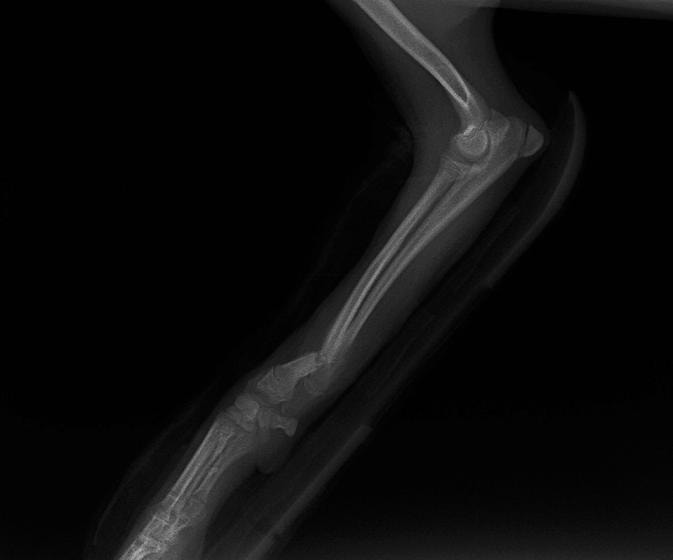

症例3:キルシュナーワイヤーのピンニングによる整復

ペルシャ猫 11ヶ月齢 雄

他院にて左大腿骨遠位の成長板骨折(salter-harrisⅠ型)が認められており、治療相談を目的として来院。当院にて、キルシュナーワイヤーを用いたピンニングにより骨折部位の整復を行いました。術後の経過は良好で、現在も経過観察中です。

術前レントゲン

術後レントゲン